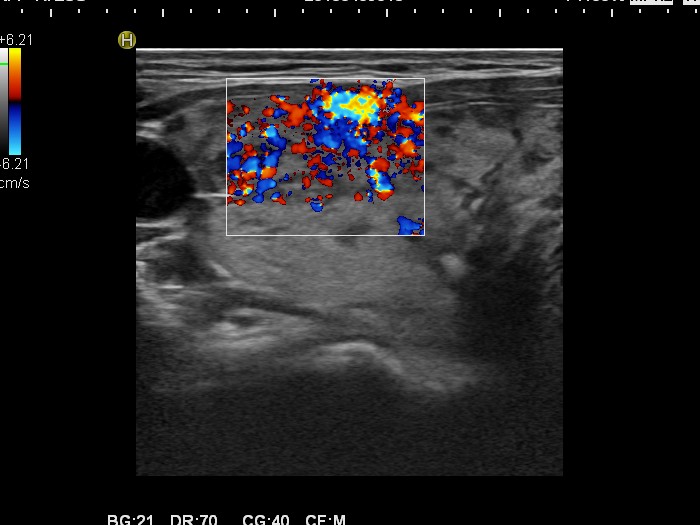

Graves' disease - Case 15.

Follow-up investigation 30 months after first visit (ultrasonographic picture 3)

Patient one year after discontinuation of thyrostatics in hyperthyroid state

Right lobe, horizontal scan, Doppler mode. The vascularization is increased.